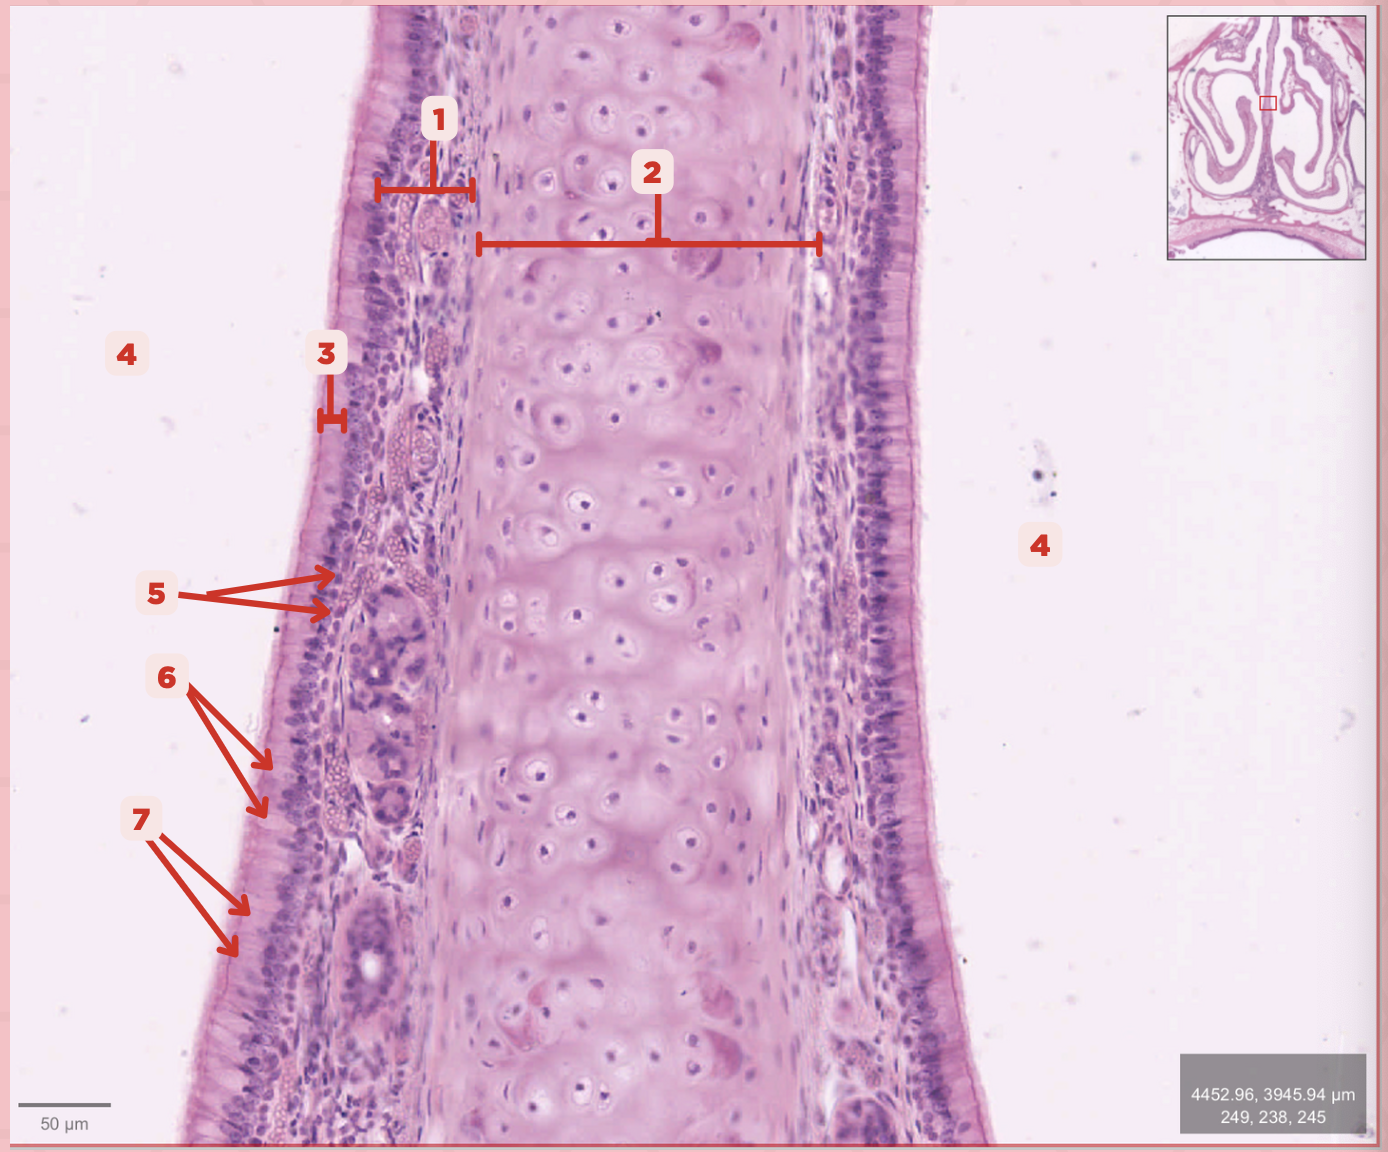

Identify the structure labeled as 1.

Hyaline Cartilage

Identify the structure labeled as 2.

Respiratory Epithelium

Identify the structure labeled as 3.

Nasal Cavity

Identify the structure labeled as 4.

Basal Cells

Identify the structure labeled as 5.

Goblet Cells

Identify the structure labeled as 6.

Ciliated Columnar Cells

Identify the structure labeled as 7.

Adipose tissue

What type of tissue is sometimes seen between the bony spicules?

Serous and Mucous Glands

What glands are present in the Lamina Propria?